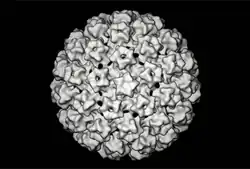

| Bovine papillomavirus (3D reconstruction) | |

Like other papillomaviruses, BPVs are small non-enveloped viruses with an icosahedral capsid around 50–60 nm in diameter.[2][3] The capsid is formed of the L1 and L2 structural proteins, with the L1 C-terminus exposed.[2][4]